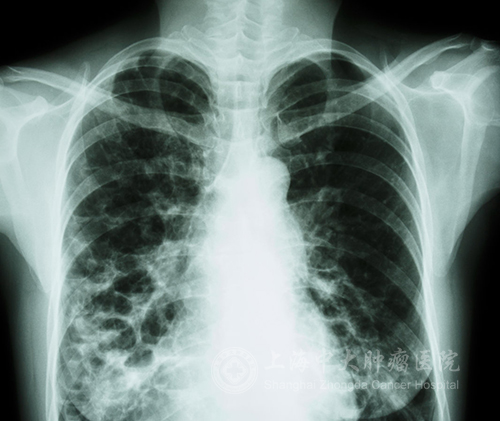

肺癌患者在治疗过程中有较长时间反映有胸闷等症状,无法缓解而且不断加强,肿瘤医生需要明确是否是由胸腔积液引发的。医生可以通过症状、呼吸音变化、叩诊以及影像检查方式进行确诊。

最为明确的诊断方式是通过抽取胸腔积液进行病理化验,检查其中是否含有癌细胞。